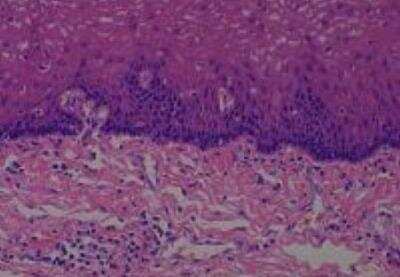

Hematoxylin & Eosin Stain: Human Common Tissue MicroArray (Normal Adjacent) [NBP2-30215] - 01. Stomach